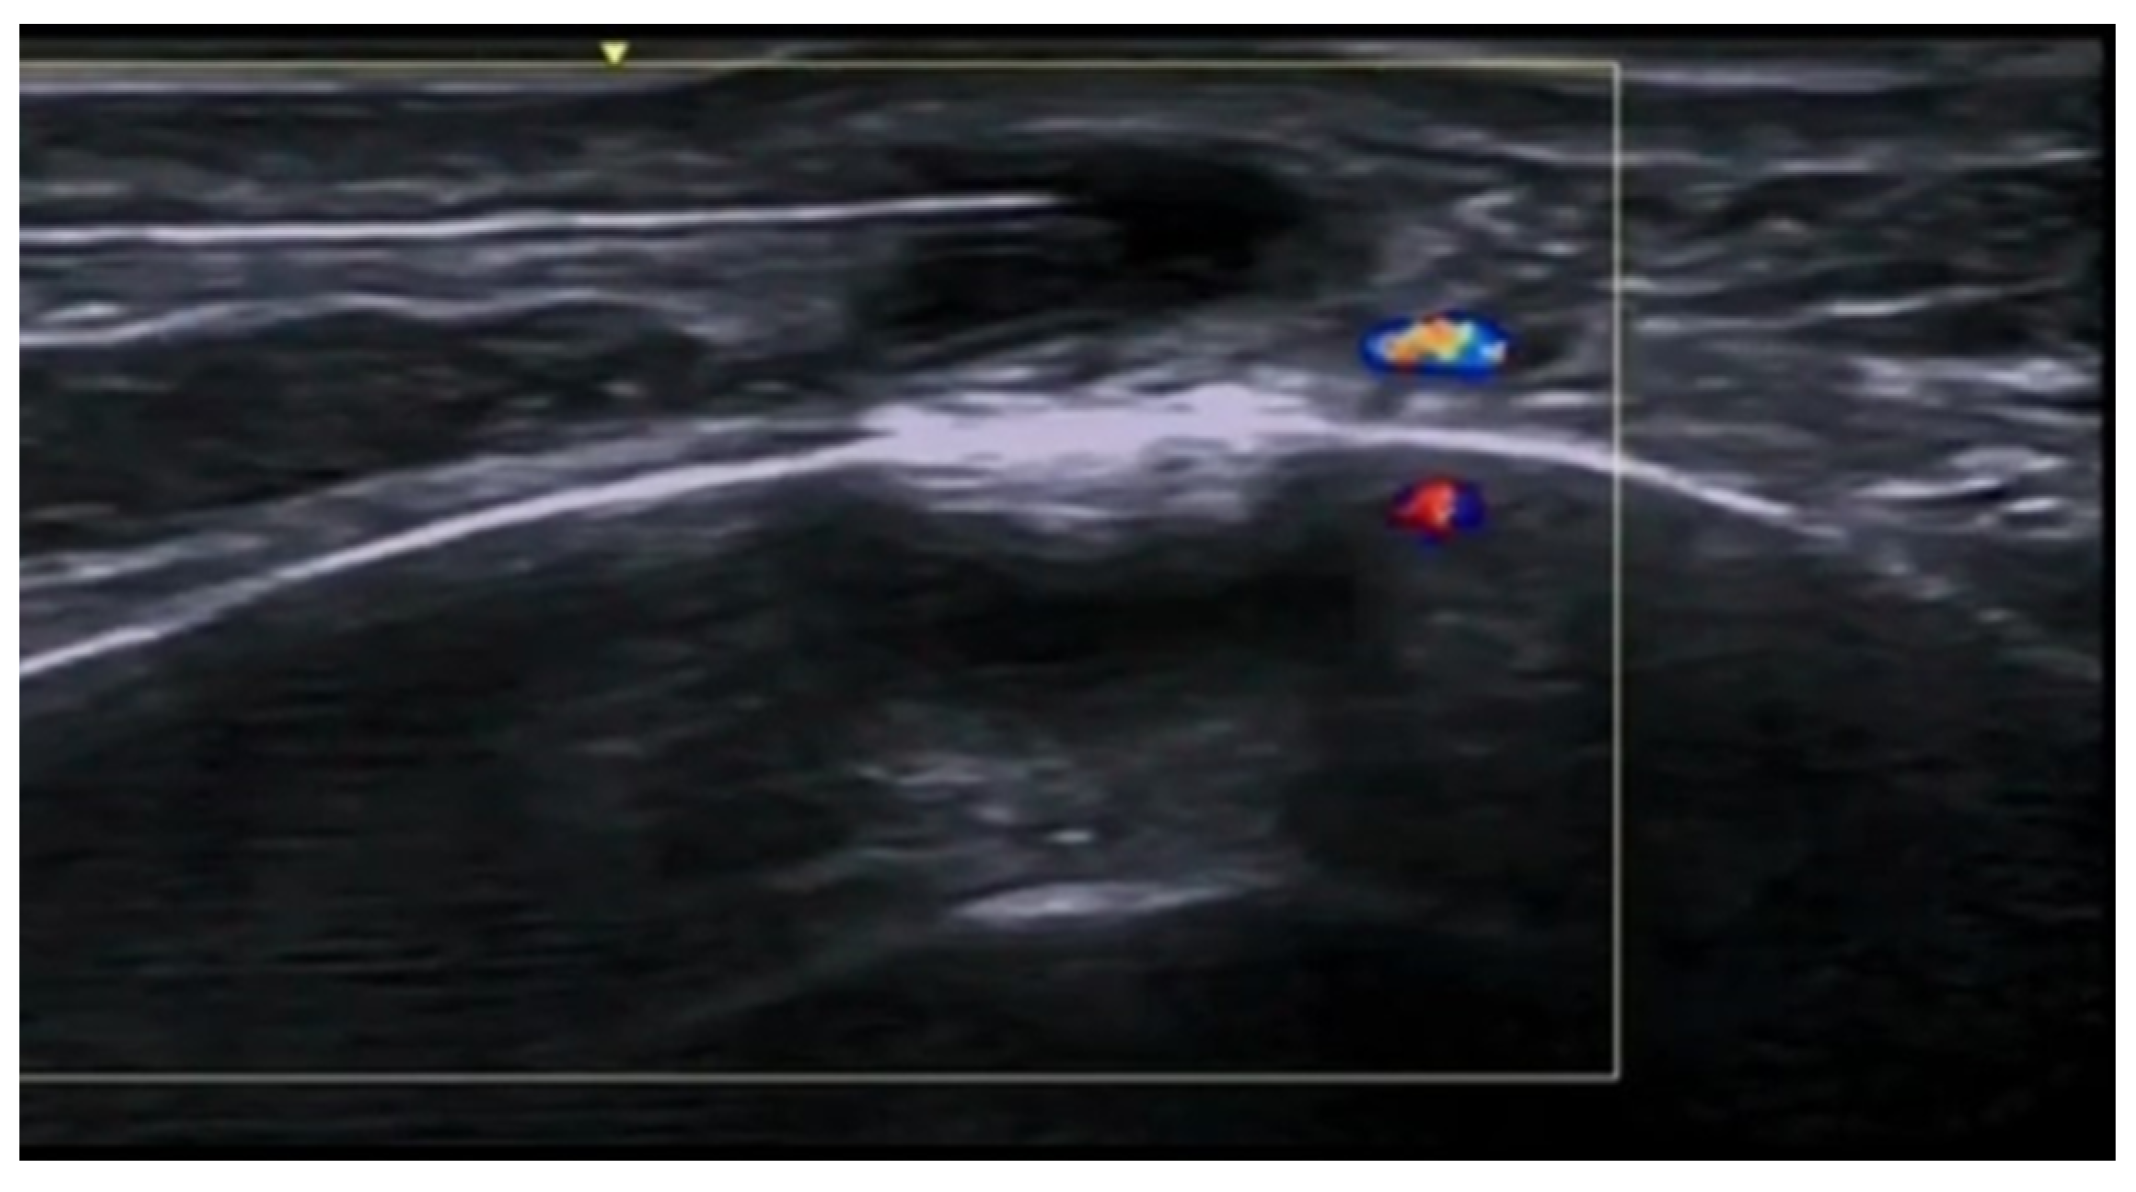

- Velthuis, P.J.; Jansen, O.; Schelke, L.W.; Moon, H.J.; Kadouch, J.; Ascher, B.; Cotofana, S. A Guide to Doppler Ultrasound Analysis of the Face in Cosmetic Medicine. Part 1: Standard Positions. Aesthetic Surg. J. 2021, 41, NP1621–NP1632. [Google Scholar] [CrossRef]

- Vasconcelos-Berg, R.; Izidoro, J.F.; Wenz, F.; Müller, A.; Navarini, A.A.; Sigrist, R.M.S. Doppler Ultrasound-Guided Filler Injections: Useful Tips to Integrate Ultrasound in Daily Practice. Aesthetic Surg. J. 2023, 43, 773–783. [Google Scholar] [CrossRef]